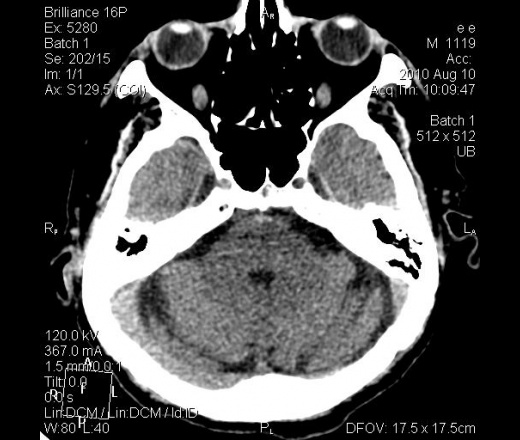

От 10.08.10 г.: В лобной доле левого полушария головного мозга кнаружи от переднего рога левого бокового желудочка гиподенсивная зона неправильной формы. В остальном картина соответствует возрасту. От 13.08.10 г.: на мой взгляд, плотность указанной зоны ещё уменьшилась и появился гиподесивный учаток в височной доле левого же полушария. Заключение: КТ-картина ишемических инфарктов в левом полушарии головного мозга различной степени давности.

Спасибо dok-a и Сергею Николаевичу за мнения. Я выставила ишемический инсульт. Первый раз, когда пациент (кстати, врач) пришел сам, была легкая оглушенность. Второй раз привезли на каталке, галлюциноз. За несколько дней консультирован и нашими, и областными неврологами. Не укладывалась клиника только в инсульт. Ликвор, взятый у нас - без особенностей. Мне показалась не совсем нормальной картина для инсульта на КТ. Но для постановки диагноза интуиции мало. Через 3 дня после поступления фербильная t. Кашель, сухие и влажные хрипы. В легких застойные дела. На КТ-контроле появилась зона ишемии в базальных отделах левой височной доли (предрекаемая неврологами по клинике и невидимая на первичной КТ). Переведен в область уже с судорогами. Через 2 недели возвращен к нам с верифицированным диагнозом ГЕРПЕТИЧЕСКОГО ЭНЦЕФАЛИТА. Учитывая редкость заболевания, выставляю здесь.